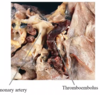

What does lung bullous rupture cause?

Pneumothorax

What is bronchiectasis?

Permanent abnormal dilatation of bronchi with inflammation and fibrosis into adjacent parenchyma